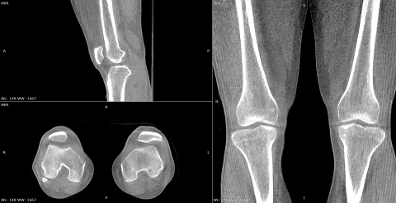

国内数字化X线头部厂商安健科技则在数字化三维化技术上创新路径,推出WR-3D多角度扫描与重建技术。在功能方面WR-3D不仅支持站立位的3D检查,可获取平躺状态下无法获取的影像信息。WR-3D装机后无需进行几何校正,降低用户的学习和使用成本。支持2D+3D一站式检查,降低CT工作负荷,提高诊疗效率。通过传统2D平面扫描后,可以直接进行站立位3D扫描,提供更多的平片或MR可能无法获得的治疗信息。WR-3D从动态DR切换到3D功能,只需要推动移动站台到指定位置即可。扫描完后,将移动站台移开即可。移动站台采用简约紧凑设计(一般家用立式空调内机大小),不占用空间。除此之外,WR-3D支持同时扫描双足,通过比较两侧脚踝,从而发现差异。还可以轻松扫描双膝关节,双髋关节。以及它能输出MPR/MIP/VRT专业重建图像,真实细腻,并支持各种测量。支持多种断层厚度、断层间隔、FOV重建,设置方式简单快捷,和传统螺旋CT设置方式类似,直接降低用户学习成本。

在性能方面,WR-3D融合安健科技成熟的低剂量动态成像技术,每秒以12-15帧的曝光速度,大约0.8s曝光一次,从扫描开始到出图,快速完成。此外,安健科技自主开发的GPU加速技术,一次获取断层图/MPR/VR图像,简单快捷。不同于西门子的等中心扫描,WR-3D采用非等中心扫描方式,病人靠近平板探测器一侧,最大支持35cm的扫描视野(FOV),一次扫描轻松容纳病人双侧髋关节。同时支持针对不同体型和部位设计不同的曝光参数,用户在界面上只需要简单选择即可,就像拍平片一样简单。可以说,WR-3D搭载的自主研发动态平板,不仅可以定位下肢术前规划和术后评估随访,利用负重位下的形态学差异,更好地指导手术。

(安健科技WR-3D扫描与重建影像)